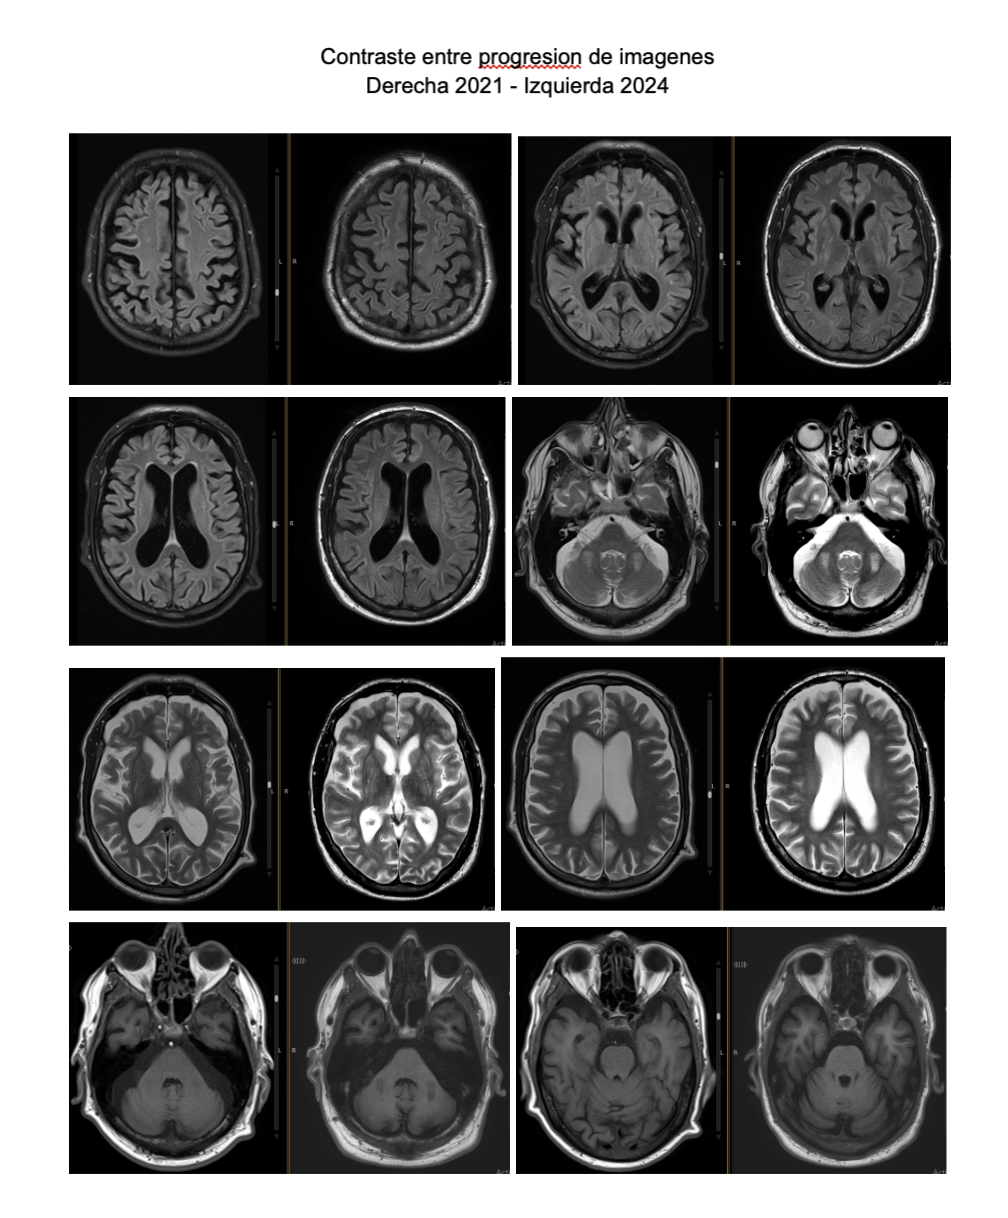

Background: Acquired hepatocerebral degeneration (AHCD) may develop following multiple instances of liver failure or persistent cirrhosis. Patients with AHCD exhibit a diverse clinical presentation, mostly characterized by movement disorders including parkinsonism and oromandibular dyskinesias. Nevertheless, the presence of additional anomalies may complicate the diagnosis. Common neuroimaging results demonstrate T1 hyperintensity in the basal ganglia. A variable percentage of patients may exhibit atypical anomalies in different anatomical regions.

Magnetic resonance imaging (T1 sequence) revealed hyperintensity in the basal ganglia and cerebellar peduncles

Conclusion: This case underscores the neurological clinical heterogeneity in patients with chronic liver disease and suggests the cerebellum as an additional target organ, alongside the basal ganglia, for manganese accumulation resulting from portosystemic shunting associated with chronic cirrhosis.

RMN Images